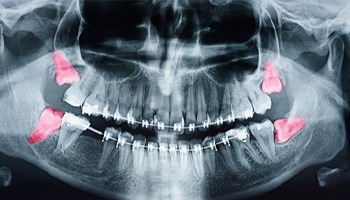

Wisdom teeth are the third set of molars at the very back of the mouth. Most people have four of them – one in each quadrant of their mouth. However, some people have only one or two.

Wisdom tooth removal is not always necessary, but that changes when these teeth pose a threat to a patient’s oral health. If your wisdom teeth are currently causing any of the following problems, or it is deemed likely they will do so in the future, your dentist in Barnegat will recommend you get them extracted:

- Overcrowding: The wisdom teeth can push against your other teeth causing overcrowding and misalignment.

- Cysts and tumors: Cysts can form when fluid builds up around a tooth. This can damage the jawbone and shift the tooth out of place.

If your wisdom teeth have fully erupted, we may utilize basic extraction techniques to remove them. That means we will use dental forceps and an elevator to gently extract them.

However, if the teeth are fully or partially impacted (stuck beneath the gumline), surgical techniques might be required to get them out. In that case, Dr. G will refer you to an excellent oral surgeon.